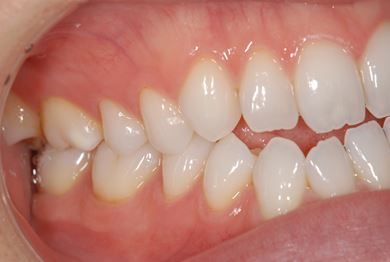

性別/年齢 女性 / 32歳

主訴 銀歯を白い歯にしたい。

治療方針 セラミック治療にて、審美的回復を行う。

治療内容 ハイブリッドセラミッククラウン1本、ハイブリッドセラミックインレー1本

治療前